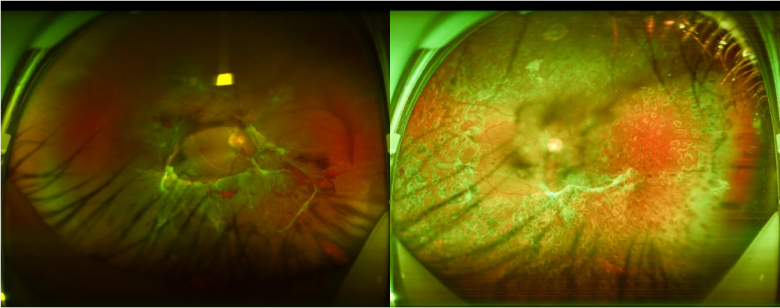

36岁的温先生,身材肥胖,日常酷爱甜食、油腻的食物。近日,温先生右眼视力视力忽然骤降,”接诊时,我们初步怀疑是视网膜脱落,经过系统检查后,发现他更像是糖尿病视网膜病变。”佛山爱尔眼科医院总院眼底病科主任赵抒羽说。经眼底荧光血管造影、血糖、糖化血糖蛋白检查后发现,温先生由于血糖升高,高血糖影响造成了眼底视网膜血管损害,需经手术治疗来降低失明的发生率。医生建议其先到综合医院降血糖,调整到正常数值后再回来安排手术。

左图为右眼术前情况,右图为右眼术前情况

视网膜在人的眼睛中相当于照相机底片一样重要,视网膜上分布了许多血管。糖尿病使视网膜血管长期处于高糖环境中,极易发生病变。这种病变就是糖尿病视网膜病变。且随着糖尿病病程越长,糖网的患病率越高。梁先军提醒,糖尿病视网膜病变初期无症状,易忽视,但随着病程的发展,视物逐渐模糊,继而引发失明。

佛山爱尔眼科医院总院梁先军表示,长期奶茶碳酸饮料,会导致体内的糖分不断累积,血糖就容易升高,造成体内代谢紊乱,最终导致患有糖尿病!糖尿病看起来和眼睛没有太大的关系,但长期、慢性的高血糖会引起血管的氧化应激及炎症反应,逐渐引起视网膜微血管的损伤,进而发生出血、水肿、渗出等临床表现,所以大家要控制少喝奶茶!